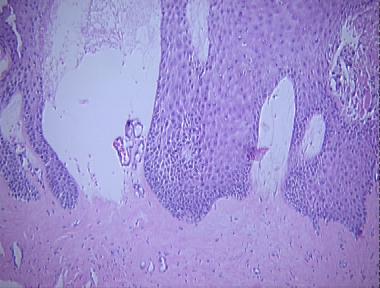

bullous scleroderma

Histologic Features